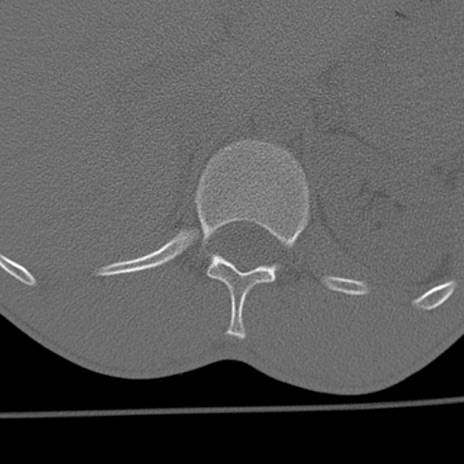

症例3 腰椎CT(横断像)

腰椎CT